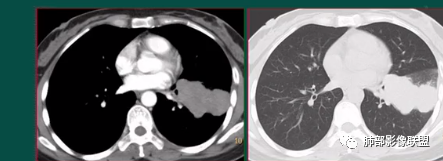

上图,鳞癌,腔内软组织占位,局部膨大,不均匀强化,伴远端粘液栓。

上图,小细胞肺癌,病灶从肺门朝外沿支气管爬行,呈指套样改变,病灶周围阻塞性肺炎较轻。

上图,粘液表皮样癌,支气管腔内病灶轻中度强化。

上图,类癌,支气管腔内占位,强化明显,远端粘液栓。

上图,支气管结石(红箭头),远端阻塞性炎症,腔内粘液栓。